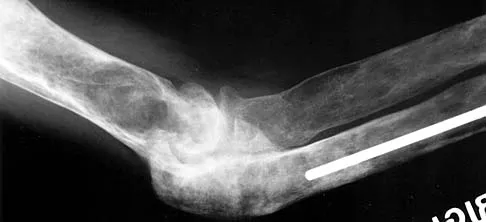

Figure 27 shows the radiograph of a 26-year-old man who sustained a closed head injury and a closed elbow dislocation 6 weeks ago. Examination reveals 65 degrees to 115 degrees of flexion, and intensive physical therapy has resulted in no improvement. A decision regarding the timing of surgical correction of the contracture should be based on

The patient has heterotopic ossification, a more common finding in patients who have sustained head injuries. Treatment will require removal of the heterotopic bone and anterior and posterior capsulectomies. The main concern about timing is the possible recurrence of heterotopic bone. While an extended wait was once thought necessary, this is no longer true. The timing is based on the time since injury and evidence of bone maturation on plain radiographs. A sharp marginal demarcation of the new bone and a trabecular pattern within it are usually present 3 to 6 months after onset, indicating that it is safe to proceed with surgical excision. It is not necessary to wait more than 6 months. Bone scan results are not good indicators because they may remain "hot" for long periods of time. The levels of alkaline phosphatase and serum calcium-phosphorus product do not need to be measured.